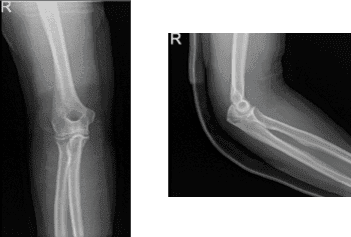

After the surgery, the patient was seen for a follow up check up and presented an X-ray result for right elbow that showed normal right elbow radiographs.

Right elbow x-ray